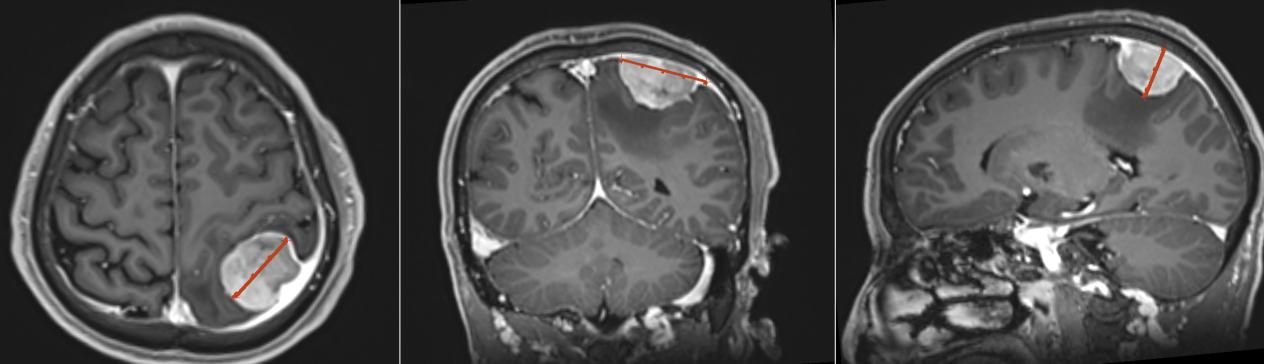

患者满某今年56岁,龙山县人,因头痛头晕半月,发现颅内占位1周入院治疗,经完善MRI等检查后提示颅内左侧顶叶占位。

神经外一科主任向昌华带领团队利用数字医学技术对满某的颅内病灶进行三维重建,结果显示颅内占位大小约3.1*4.0*2.2cm,邻近中央后回的人体感觉功能区。考虑满某正值盛年,若不及时手术治疗放任肿瘤继续生长,将会带来更加严重的神经功能隐患,如感觉障碍、肢体偏瘫等。经过反复沟通后,患者及家属同意手术方案。

MRI提示左侧顶部占位性病变,考虑脑膜瘤